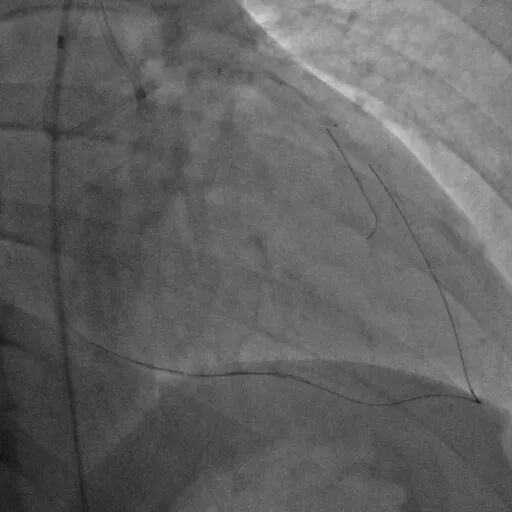

使用P200导丝攻击远端纤维帽前进困难,更换G3进入LAD近段内膜下,直接使用Telescope™导引延长导管辅助下AGT技术,r-CART后G3顺利进入Telescope™导引延长导管。

直接使用G3导丝rendezvous,球囊扩张后行IVUS检查确定血管直径及支架落脚点。

D1释放DCB,LAD植入支架后D1血流影响,工作导丝找回后使用球囊扩张并kissing。

造影发现LAD远端病变仍较重,释放DCB。

复查造影并行ivus检查 支架贴壁良好 无累及夹层。